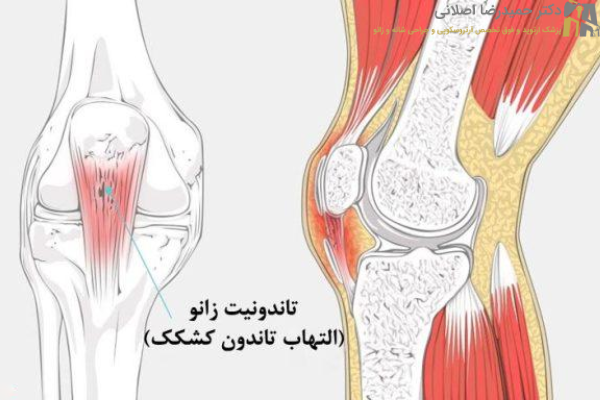

تاندونیت زانو چیست؟

تاندونیت زانو به التهاب و آسیب دیدگی تاندون های اطراف مفصل زانو گفته می شود. به طور دقیق تر، این مشکل بیشتر تاندون کشکک را تحت تاثیر قرار می دهد. این تاندون درست جلوی زانو قرار دارد و استخوان کشکک (کاسه زانو) را به قسمت بالایی استخوان درشت نی (یکی از استخوانهای اصلی ساق پا) متصل می کند. به همین دلیل گاهی از این عارضه تحت عنوان تاندونیت کشکک زانو هم یاد می کنند.

کار اصلی تاندون های زانو، کمک به حرکت پا مثل صاف کردن زانو است. وقتی این تاندون ها ملتهب یا آسیب دیده می شوند، انجام این حرکات دردناک و سخت خواهد شد. این وضعیت نوعی آسیب ورزشی به حساب می آید اما ممکن است برای هر فردی پیش بیاید.

تاندونیت زانو بیشتر به التهاب تاندون کشکک اشاره دارد اما بر اساس شدت و مدت مشکل از اصطلاحات مختلفی استفاده می شود:

- تاندونیت کشکک (Patellar Tendinitis): این رایج ترین نوع تاندونیت زانو بوده و به التهاب حاد (کوتاه مدت) تاندون کشکک در اثر آسیب یا فشار زیاد اشاره دارد.